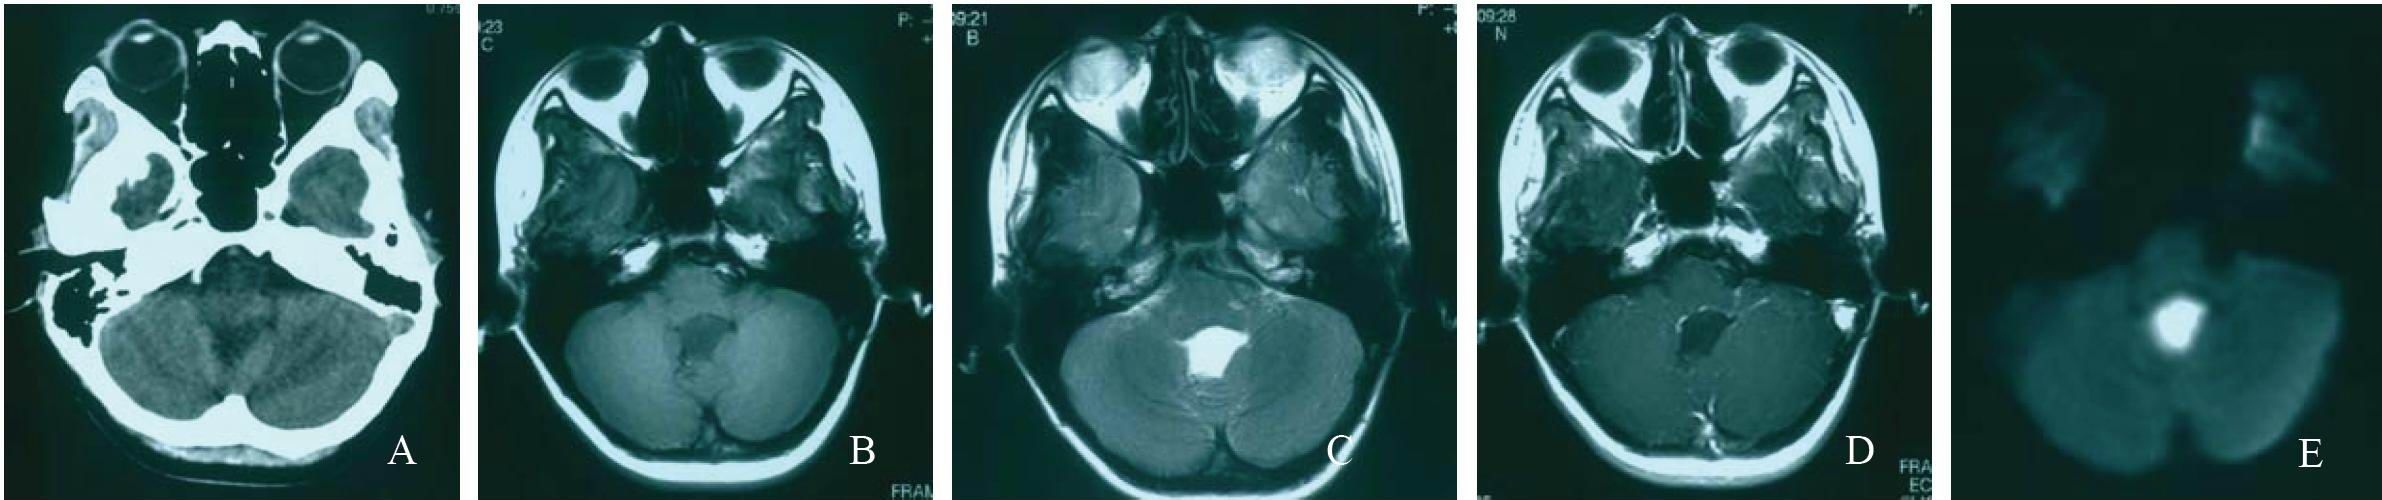

颅内胆脂瘤, 即颅内表皮样囊肿或珍珠瘤, 约占颅内肿瘤的2% 左右.

颅内胆脂瘤,是一种缓慢生长的良性肿瘤,好发于颅底的蛛网膜下腔区域.